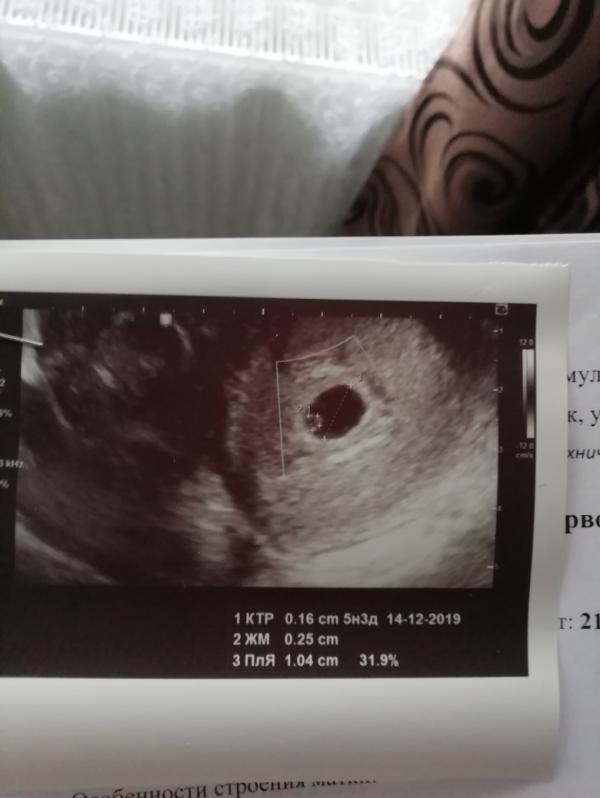

Первое фото малыша😍

Через неделю на повторное, чтобы отследить динамику роста и засеч сердцебиение ❤️ очень переживаю...